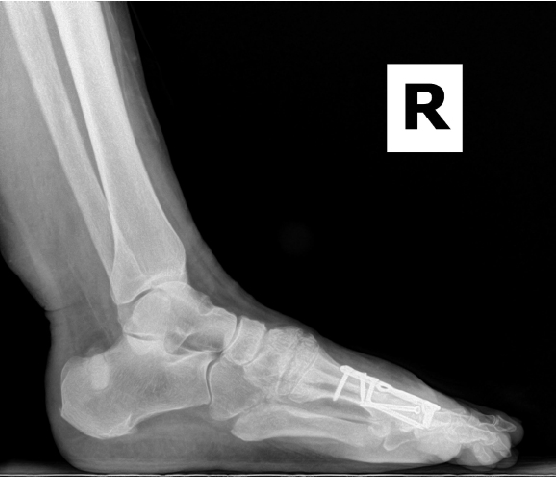

Therefore, most surgeons use common radiographic signs to rule out primary delay and eventual non-union. Some of these signs include the presence of a bridging callus, three of four cortices being bridged by callus formation and the resorption of fracture lines.2 Evaluation of the hardware across the proposed fusion site is also a good indicator. Hardware failure often indicates motion across the site with a lack of bony union, which places more force on the hardware, resulting in failure. Radiographic assessment is limited to the rate at which bony changes are visible in radiographs, which can take months.

Conversely, surgeons should also attend to the factors they can control. Ensure a stable rigid construct; augmentation of osteogenic, osteoinductive or osteoconductive properties; and establishment and maintenance of a normal anatomic alignment when possible. With the development of more anatomic contouring for internal and more “user-friendly” external devices, there are a variety of options available to choose from when determining how to obtain stable and rigid alignment. A combination of both plates and screws is often indicated to prevent any micromotion across the fusion site.